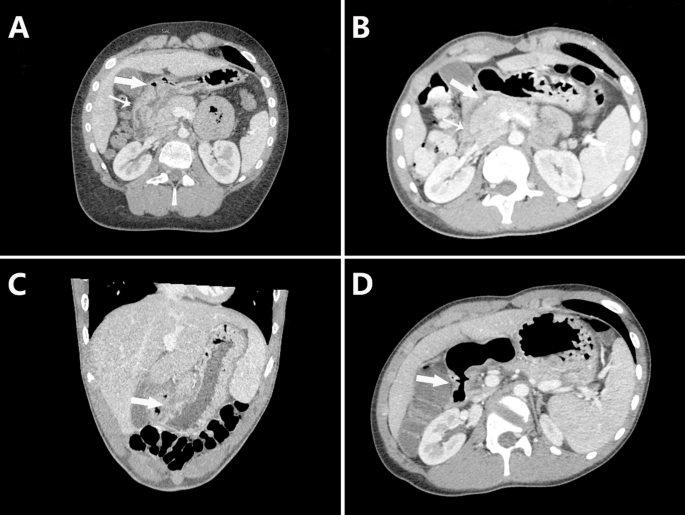

Radiological findings

Twenty-four patients underwent enhanced abdominal CT: 23 showed duodenal bulb wall thickening with abnormal mucosal enhancement, and 8 had gastric antral mucosal thickening. The typical imagological picture of these patients was shown in Fig. 3.

Abdominal enhanced CT examination of eosinophilic DBU. (A,B) Thickening of the duodenal bulb (large arrow) and descending part (small arrow) in case 10, with improvement after treatment. (C) Thickening of the duodenal bulb (large arrow) in case 3. (D) Thickening of the duodenal bulb (large arrow) in case 18.